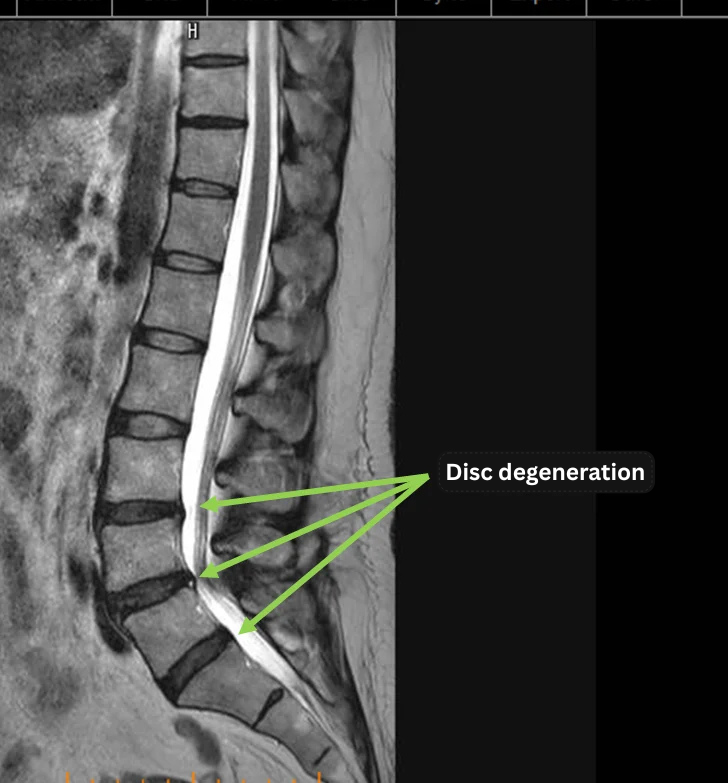

Imaging and findings

- L3,4/5,5/s – degeneration of the intervertebral discs

- L4/5 imaging shows residual findings of a previous herniation and a visible annular fissure.